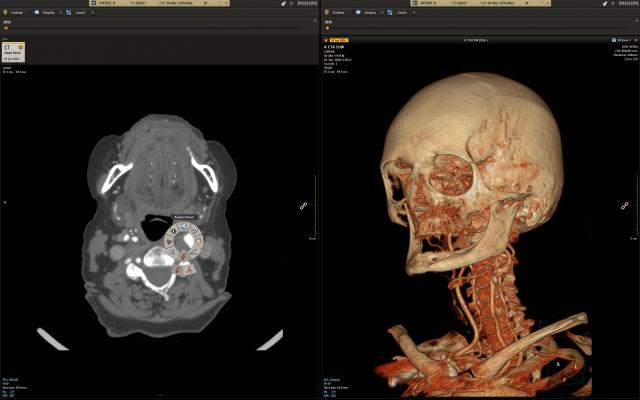

August 15, 2018 — Intel and Philips recently tested two healthcare uses for deep learning inference models using Intel Xeon Scalable processors and the OpenVINO toolkit. One use case focused on X-rays of bones for bone-age-prediction modeling, the other on computed tomography (CT) scans of lungs for lung segmentation. In these tests, Intel and Philips achieved a speed improvement of 188 times for the bone-age-prediction model, and a 38 times speed improvement for the lung-segmentation model over the baseline measurements.

AI techniques such as object detection and segmentation can help radiologists identify issues faster and more accurately, which can translate to better prioritization of cases, better outcomes for more patients and reduced costs for hospitals.

The bone-age-prediction model went from an initial baseline test result of 1.42 images per second to a final tested rate of 267.1 images per second after optimizations – an increase of 188 times. The lung-segmentation model surpassed the target of 15 images per second by improving from a baseline of 1.9 images per second to 71.7 images per second after optimizations.